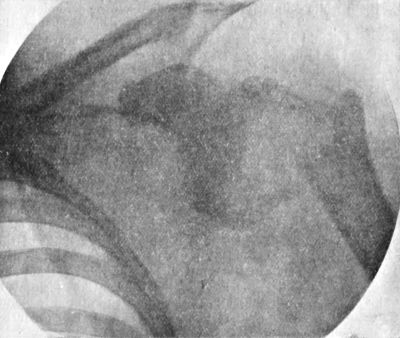

| 213. | Radiogram of Child's Thorax showing Spindle-shaped Shadow at Site of Pott's Disease of Fourth, Fifth, and Sixth Thoracic Vertebræ | 437 |